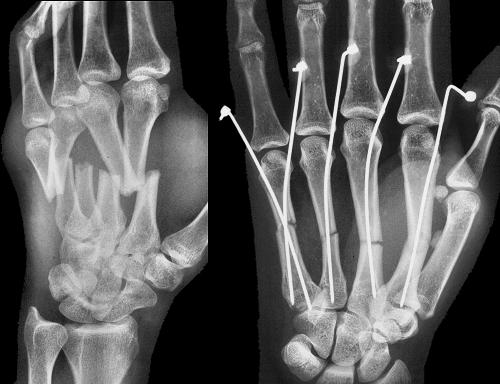

Figure Legend:

Crush injuries are prone to delayed wound healing and stiffness with

standard open reduction and internal fixation techniques. Percutaneous

fracture pinning allows fracture stabilization without the addition of

additional trauma from fracture site exposure.